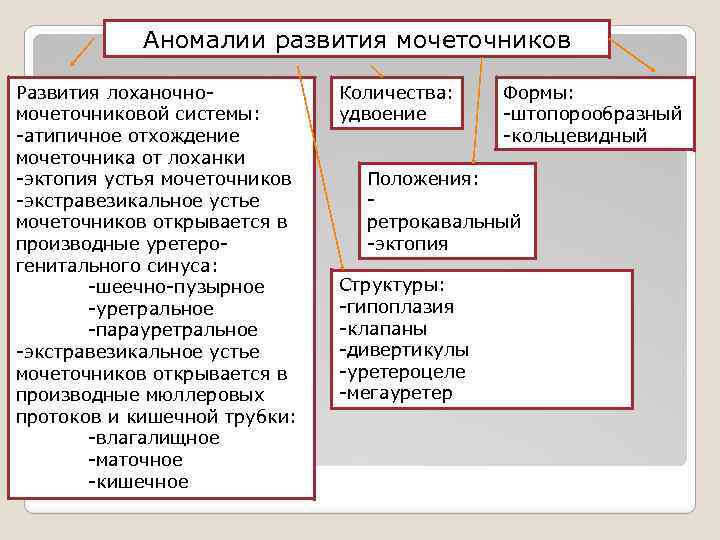

Аномалии развития мочеточников Развития лоханочномочеточниковой системы: -атипичное отхождение мочеточника от лоханки -эктопия устья мочеточников -экстравезикальное устье мочеточников открывается в производные уретерогенитального синуса: -шеечно-пузырное -уретральное -парауретральное -экстравезикальное устье мочеточников открывается в производные мюллеровых протоков и кишечной трубки: -влагалищное -маточное -кишечное Количества: удвоение Формы: -штопорообразный -кольцевидный Положения: ретрокавальный -эктопия Структуры: -гипоплазия -клапаны -дивертикулы -уретероцеле -мегауретер

Аномалии развития мочеточников Развития лоханочномочеточниковой системы: -атипичное отхождение мочеточника от лоханки -эктопия устья мочеточников -экстравезикальное устье мочеточников открывается в производные уретерогенитального синуса: -шеечно-пузырное -уретральное -парауретральное -экстравезикальное устье мочеточников открывается в производные мюллеровых протоков и кишечной трубки: -влагалищное -маточное -кишечное Количества: удвоение Формы: -штопорообразный -кольцевидный Положения: ретрокавальный -эктопия Структуры: -гипоплазия -клапаны -дивертикулы -уретероцеле -мегауретер